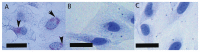

Hepatic fibrosis induced by egg deposition is the most serious pathology associated with chronic schistosomiasis, in which the hepatic stellate cell (HSC) plays a central role. While the effect of Schistosoma mansoni eggs on the fibrogenic phenotype of HSCs has been investigated, studies determining the effect of eggs of S. japonicum on HSCs are lacking. Disease caused by S. japonicum is much more severe than that resulting from S. mansoni infection so it is important to compare the pathologies caused by these two parasites, to determine whether this phenotype is due to the species interacting differently with the mammalian host. Accordingly, we investigated the effect of S. japonicum eggs on the human HSC cell line, LX-2, with and without TGF-β (Transforming Growth Factor beta) co-treatment, so as to determine the impact on genes associated with fibrogenesis, inflammation and matrix re-organisation. Activation status of HSCs was assessed by αSMA (Alpha Smooth Muscle Actin) immunofluorescence, accumulation of Oil Red O-stained lipid droplets and the relative expression of selected genes associated with activation. The fibrogenic phenotype of HSCs was inhibited by the presence of eggs both with or without TGF-β treatment, as evidenced by a lack of αSMA staining and reduced gene expression of αSMA and Col1A1 (Collagen 1A1). Unlike S. mansoni-treated cells, however, expression of the quiescent HSC marker PPAR-γ (Peroxisome Proliferator-Activated Receptor gamma) was not increased, nor was there accumulation of lipid droplets. In contrast, S. japonicum eggs induced the mRNA expression of MMP-9 (Matrix Metalloproteinase 9), CCL2 (Chemokine (C-C motif) Ligand 2) and IL-6 (Interleukin 6) in HSCs indicating that rather than inducing complete HSC quiescence, the eggs induced a proinflammatory phenotype. These results suggest HSCs in close proximity to S. japonicum eggs in the liver may play a role in the proinflammatory regulation of hepatic granuloma formation.